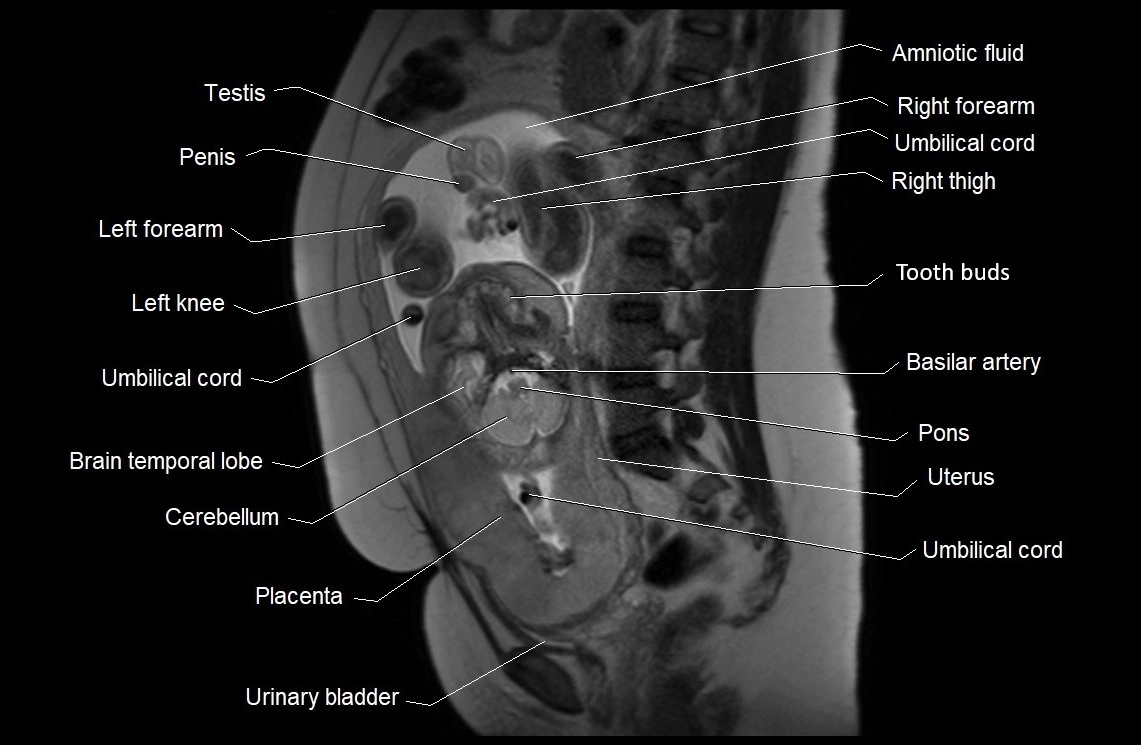

• Imaging relevance: MRI used for fetal visualization and assessing oligohydramnios/polyhydramnios when ultrasound is inconclusive

MRI Appearance

T2 HASTE (T2 GRE):

• Amniotic fluid shows very bright hyperintense signal

• Provides natural contrast against fetus and placenta

• Small particles (vernix) may appear as scattered hypointense foci within bright fluid

T1 GRE:

• Amniotic fluid shows low signal intensity (dark)

• Hemorrhage, infection, or proteinaceous content may cause focal or diffuse high signal intensity